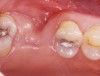

The patient was a 55-year-old woman referred for evaluation of tooth No. 30 (Figure 3A). The tooth presented with a fractured root and was deemed nonrestorable. After a full thickness flap elevation, tooth No. 30 was extracted using an elevator and forceps. It was decided to preserve the socket because the site was planned to have an implant-supported restoration. The socket was grafted using freeze-dried bone allograft mixed with CAPSET (calcium sulfate bone graft barrier).a The socket was allowed to heal for 4 months (Figure 3B). After the healing period, the patient was scheduled to have an implant placed (Figure 3C). At the time of placement, it was noted that the bone appeared to be dense and firm to the touch. The implant was placed uneventfully (Figure 3D) and was successfully restored after a 3-month healing period. The patient has been followed for over 3 years and is functioning well using the implant-supported restoration.

Figure 3b  The socket was grafted using freeze-dried bone allograft mixed with CAPSET. The socket was allowed to heal for 4 months.

Figure 3c  After the healing period, the patient had an implant placed.